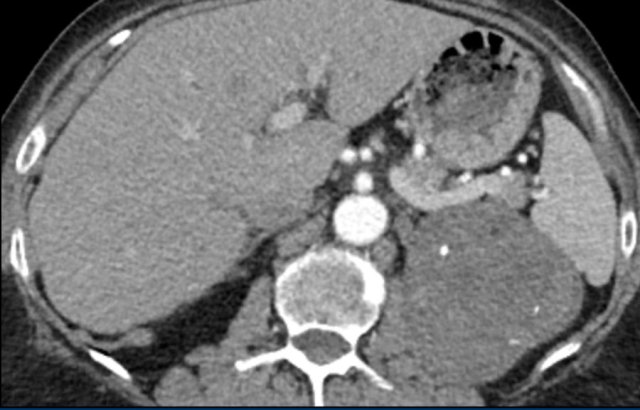

The image shows a 67 mm heterogeneously enhancing relatively well defined lesion.

This proved to be an adrenocortical carcinoma, after resection.